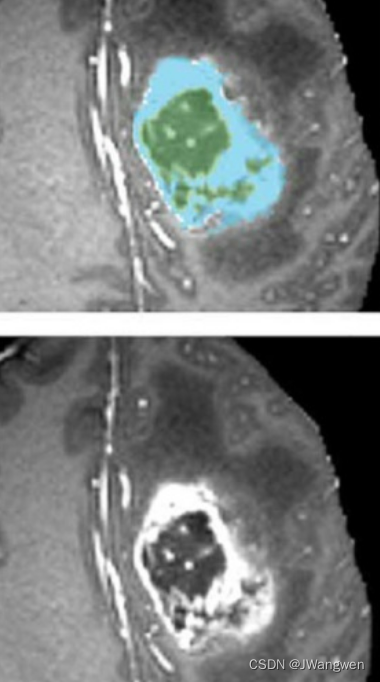

下图所示, 蓝色区域是增强瘤(enhancing tumor),它环绕的里面绿色那些是坏疽(ju)(necrotic components),坏疽就是细胞坏死然后液化.所以这些坏疽还被被称为非增强瘤(non-enhancing tumor).